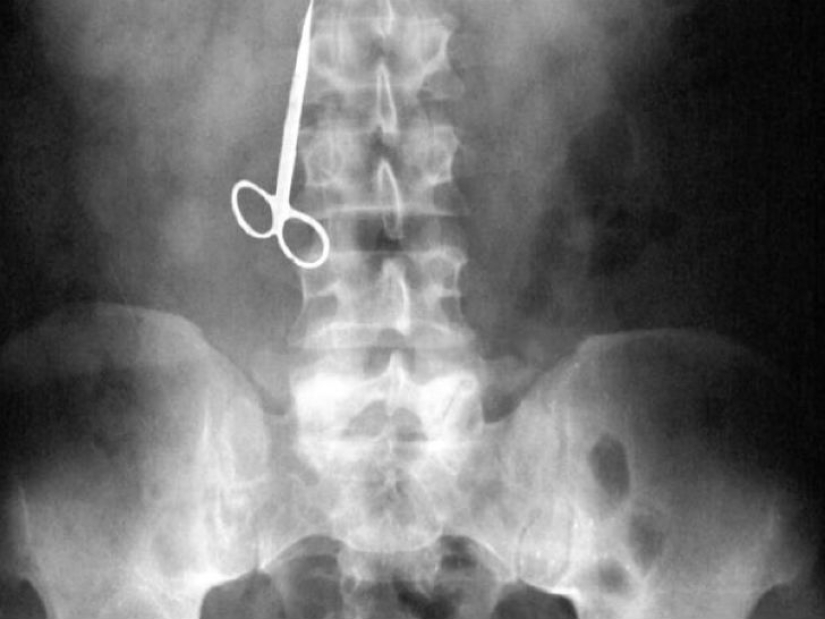

Una mujer no encontró palillos en casa después del almuerzo y decidió usar tijeras.